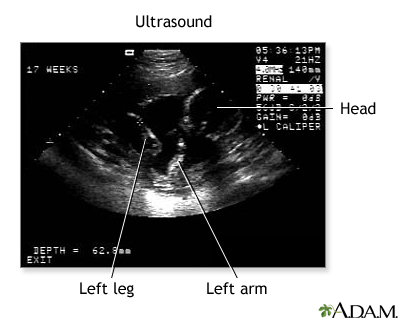

Don't get your hopes up too much about this first, fleeting look at your baby. The black-and-white image you see on the computer screen is grainy, shadowy, and may look more like a test pattern than a baby-to-be. Your sonographer will walk you through what you're seeing by pointing out the fetus' developing heart, limbs, and head.